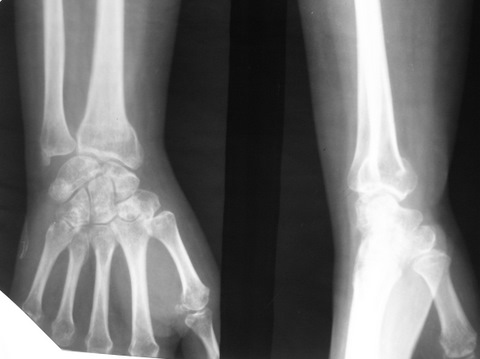

Обратилась женщина 45лет, профессия - швея, травма 24.02.07

вколоченный перелом правого луча (см Ргр Р******279). Лечилась:

На данный момент женщину беспокоят слабокупирующиеся боли

плечо-локоть-кисть по локтевой поверхности больше, ограничение

движений в л\з суставе и мелких суставах кисти (см приложения: общий

вид, объем движений  - рис. Р*******272, Р******271), на Ргр нарастают

явления остеопороза, не смотря на прием препаратов кальция(рис.

Р****277,278).